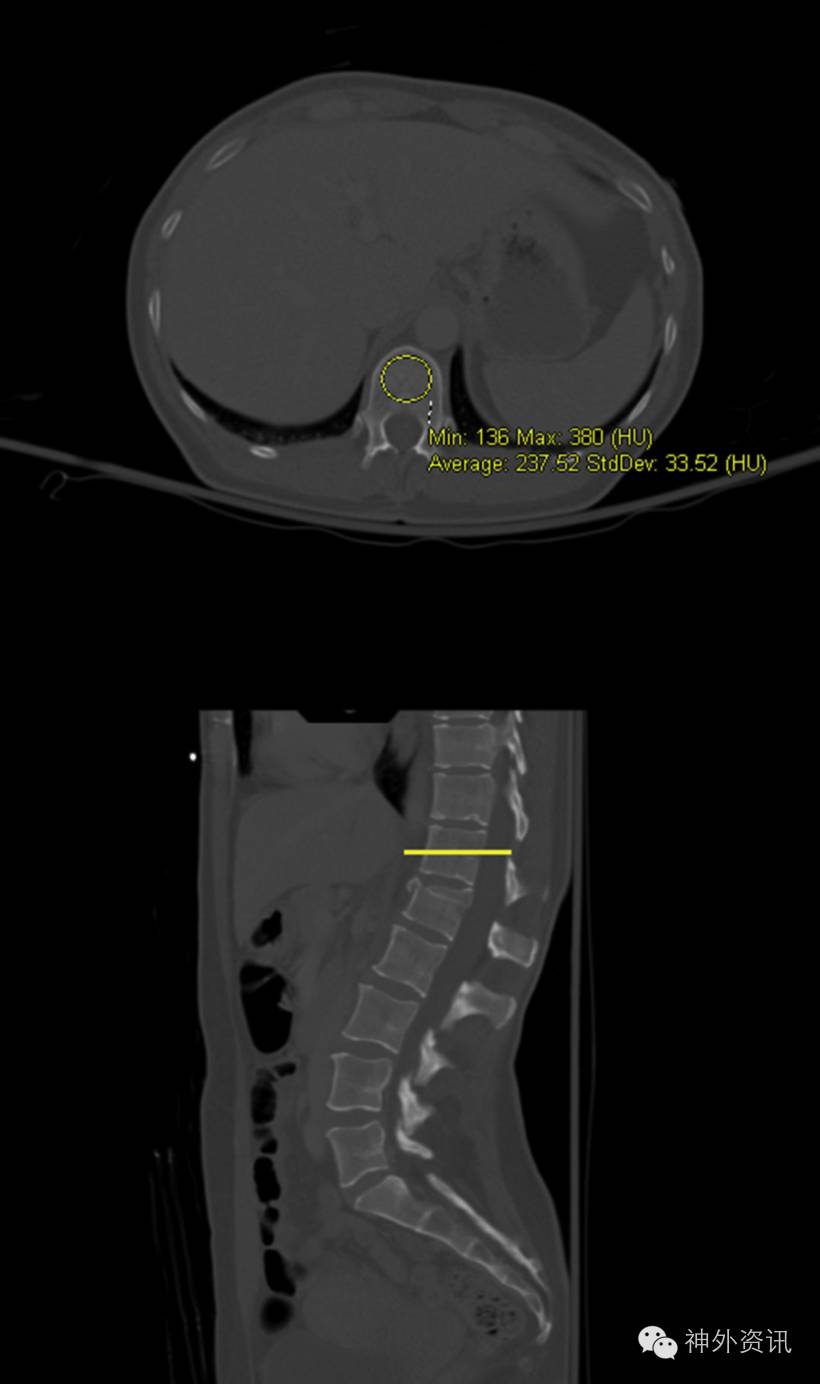

作者对2006年9月至2015年7月遭遇机动车事故导致VCF的患者进行回顾性研究。研究对象纳入标准:年龄≥18岁,L1至L4的单一VCF患者,具有影像学资料,并接受保守固定治疗。共纳入37例患者。平均CT值由椎体最大的椭圆面计算而得,不包含皮质边缘。损伤平面上、下的平均CT值用以估计VCF之前损伤面的CT值。压缩百分数定义为损伤椎体前缘高度除以其上、下椎体的前缘平均高度,该指标通过最初和随访X片获得(图1、2)。间隔百分比(Δ%)变化定义为最初X片压缩百分数减去随访X片压缩百分数。

图1. L1椎体压缩性骨折X线片。上图显示不包括皮质边缘的平均CT值测量方式。